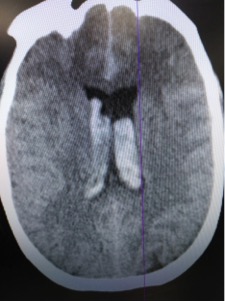

Patient was rushed to CT given clinical hx and presentation.

CT read as large amount of subarachnoid hemorrhage, suspicious for ruptured aneurysm.